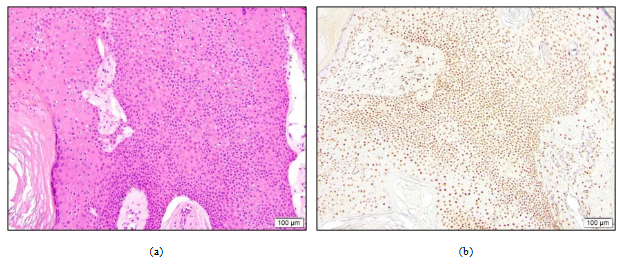

研究结果显示,TRPS1在汗腺肿瘤中的表达呈现显著差异。在恶性肿瘤中,除微囊肿性附属器癌全部为阴性外,其他类型如小汗腺腺癌 (图1)、恶性汗腺癌 (图2) 和恶性汗孔瘤 (图3) 均表现出较高的阳性率 (88%总体阳性,81%为中高表达)。

图1. 小汗腺腺癌。(a) 腺体样结构;(b) TRPS1高阳性表达。